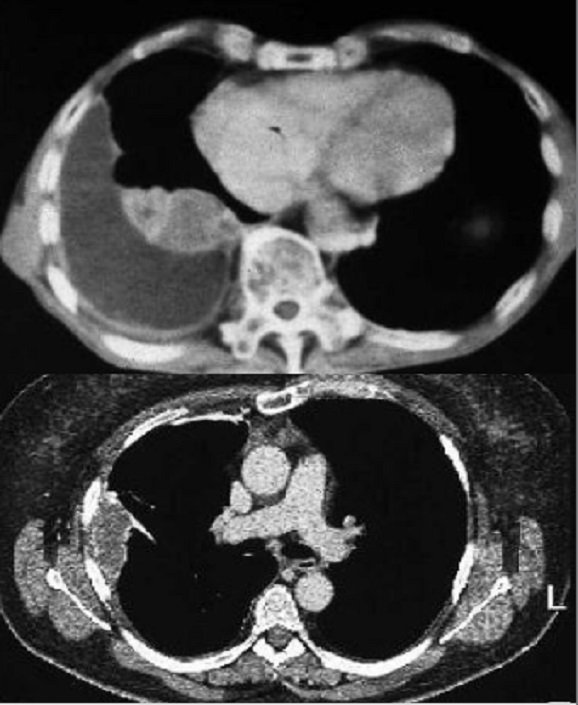

Même cas en coupe TDM axiale . Metastase

costale |

Opacite

d' origine pleurale : Image TDM

- En haute : Empyème et abces

- En bas : Mesotheliome

maligne mais envahis la paroi thoracique .